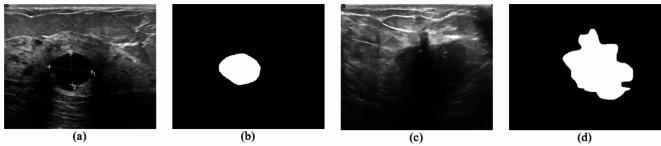

Accurate and unbiased classification of breast lesions is pivotal for early diagnosis and treatment, and a deep learning approach can effectively represent and utilize the digital content of images for more precise medical image analysis. Breast ultrasound imaging is useful for detecting and distinguishing benign masses from malignant masses. Based on the different ways in which benign and malignant tumors affect neighboring tissues, i.e., the pattern of growth and border irregularities, the penetration degree of the adjacent tissue, and tissue-level changes, we investigated the relationship between breast cancer imaging features and the roles of inter- and extra-lesional tissues and their impact on refining the performance of deep learning classification. The novelty of the proposed approach lies in considering the features extracted from the tissue inside the tumor (by performing an erosion operation) and from the lesion and surrounding tissue (by performing a dilation operation) for classification. This study uses these new features and three pre-trained deep neuronal networks to address the challenge of breast lesion classification in ultrasound images. To improve the classification accuracy and interpretability of the model, the proposed model leverages transfer learning to accelerate the training process. Three modern pre-trained CNN architectures (MobileNetV2, VGG16, and EfficientNetB7) are used for transfer learning and fine-tuning for optimization. There are concerns related to the neuronal networks producing erroneous outputs in the presence of noisy images, variations in input data, or adversarial attacks; thus, the proposed system uses the BUS-BRA database (two classes/benign and malignant) for training and testing and the unseen BUSI database (two classes/benign and malignant) for testing. Extensive experiments have recorded accuracy and AUC as performance parameters. The results indicate that the proposed system outperforms the existing breast cancer detection algorithms reported in the literature. AUC values of 1.00 are calculated for VGG16 and EfficientNet-B7 in the dilation cases. The proposed approach will facilitate this challenging and time-consuming classification task.

准确和无偏的乳腺病变分类对于早期诊断和治疗至关重要,深度学习方法可以有效地表示和利用图像的数字内容,从而进行更精确的医学图像分析。乳腺超声成像是检测和区分良性和恶性肿块的有用工具。基于良性和恶性肿瘤对邻近组织的不同影响方式,即生长模式和边界不规则性、相邻组织的穿透程度以及组织级别的变化,我们研究了乳腺癌成像特征与肿瘤内外组织的作用之间的关系,以及它们对改进深度学习分类性能的影响。所提出方法的新颖之处在于考虑了从肿瘤内部组织(通过执行腐蚀操作)和病变及周围组织(通过执行膨胀操作)中提取的特征进行分类。本研究使用这些新特征和三个预先训练的深度神经元网络来解决超声图像中乳腺病变分类的挑战。为了提高模型的分类准确性和可解释性,所提出的模型利用迁移学习来加速训练过程。使用三个现代预先训练的 CNN 架构(MobileNetV2、VGG16 和 EfficientNetB7)进行迁移学习和微调优化。存在神经元网络在存在噪声图像、输入数据变化或对抗攻击时产生错误输出的问题;因此,所提出的系统使用 BUS-BRA 数据库(良性和恶性两类)进行训练和测试,使用看不见的 BUSI 数据库(良性和恶性两类)进行测试。大量实验记录了准确性和 AUC 作为性能参数。结果表明,所提出的系统优于文献中报道的现有乳腺癌检测算法。在膨胀情况下,VGG16 和 EfficientNet-B7 的 AUC 值计算为 1.00。所提出的方法将有助于这项具有挑战性和耗时的分类任务。